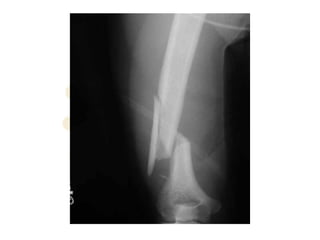

Radial Nerve Palsy

• Causes:

– Fractures esp humerus, Monteggia

– Penetrating injury/trauma

– “Saturday Night Palsy” “Crutches”

– Iatrogenic

– tumour